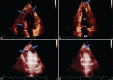

Cardiac Metastasis of Malignant Melanoma